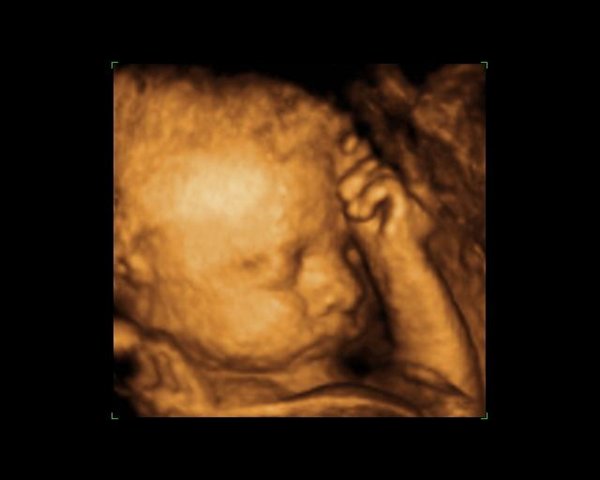

Dernæst havde vi bestilt tid til en privat 3d/4dscanning på scanningsklinikken i København, men den første gang lå hun med hænderne foran ansigtet, så vi blev tilbudt en ekstra gratis.. Det samme skete så anden gang igen og så var de så søde at vi fik en tredje gang, og så kunne vi endelig se hendes smukke ansigt